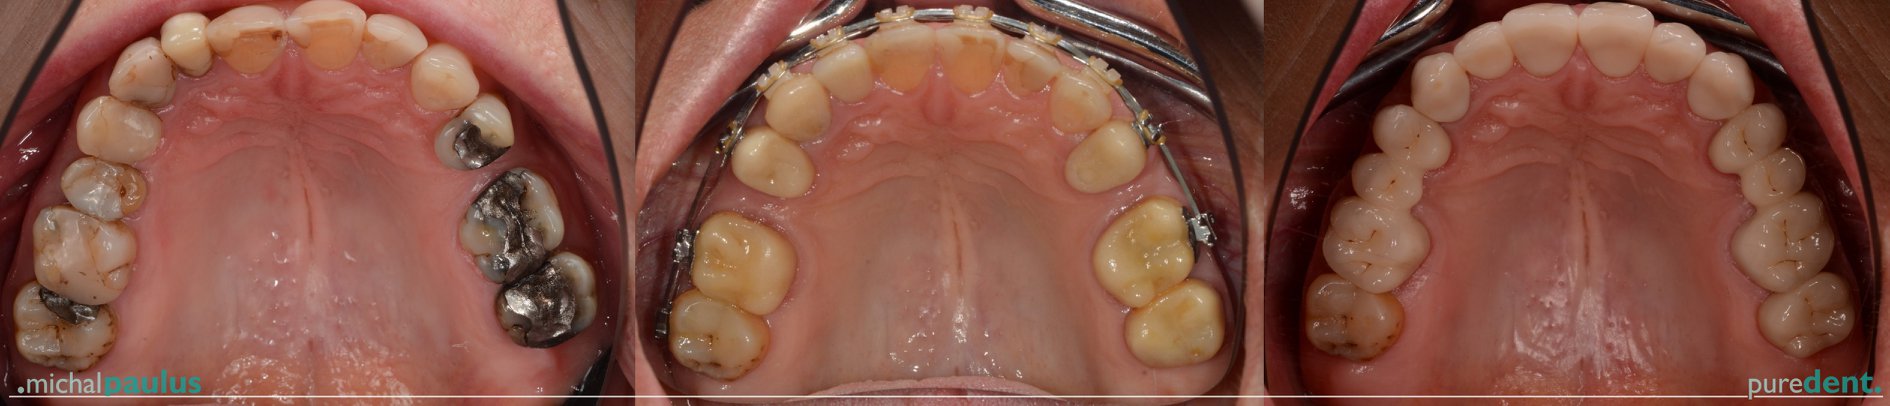

Celková rekonstrukce chrupu

Celkové rekonstrukce chrupu

Celková rekonstrukce chrupu Celková rekonstrukce chrupu Celková rekonstrukce chrupu Celková rekonstrukce chrupu